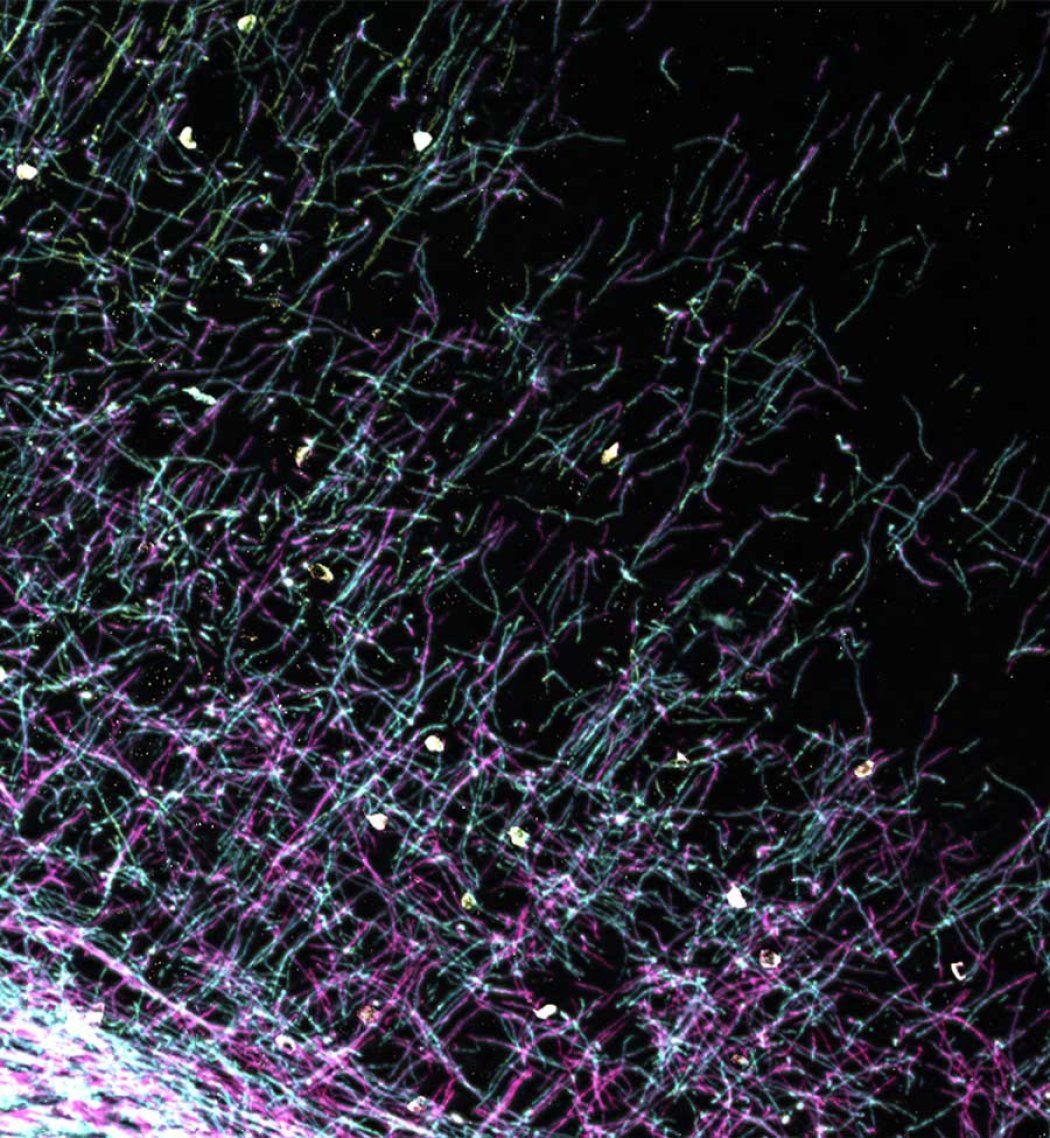

Poon used MT7 to engineer a molecular label for M1R that revealed rings of OPCs gathering around damage in a mouse model of MS and in human MS tissue.